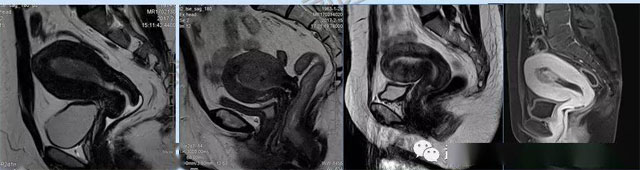

婦科疾病常常讓女性陷入了焦慮。主要是這類疾病婦女有難言之隱,癥狀隱匿,病情復雜。磁共振體檢車的金光火眼能力可以破解各種婦科難題。哪些情況需要使用磁共振檢查,檢查過程是否有不適。這些都是可以解決的。例如子宮常見疾病的磁共振診斷。

磁共振VS傳統(tǒng)檢查:有這些優(yōu)勢?無輻射安全系數高,磁共振沒有電離輻射,適合備孕跟孕婦檢查。它對軟組織有高清的成像效果,可以清晰的看到子宮各層的結構??梢宰R別細小的肌瘤,早期的癌癥腫瘤。可以發(fā)現其他設備難以檢查到的深部子宮內膜異位結節(jié)。多序列成像和增強掃描檢查,判斷腫瘤的良性準確率高達90%以上。

磁共振檢查可以對子宮內膜癌,精準測量腫瘤侵犯子宮肌層的深度,發(fā)現微小轉移灶。復雜子宮肌瘤明確肌瘤位置、數量,區(qū)分良性肌瘤與惡性肉瘤,幫助制定微創(chuàng)手術方案。卵巢腫瘤鑒別數值分析、增強掃描,可識別畸胎瘤、巧克力囊腫、惡性腫瘤的特征。宮頸癌分期,判斷腫瘤大小、是否侵犯膀胱/直腸,指導選擇手術或放化療。生殖道畸形三維成像直觀顯示畸形類型,為矯正手術或輔助生殖提供依據。